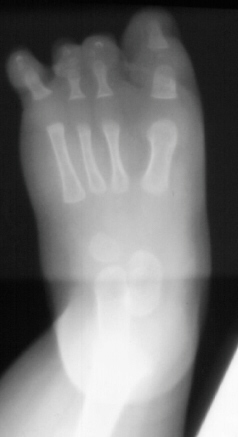

The

correct diagnosis for this pattern of deformity is proximal femoral

focal deficiency (PFFD).

This

is a common combination of deformities.

insult that causes these deformities occurs between weeks 10 and

12 after conception.

There

is no known specific cause of these deformities.